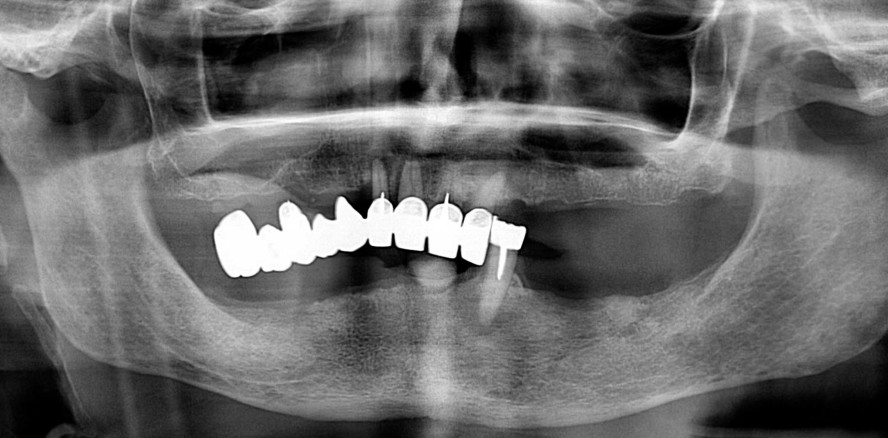

Zur Herstellung der verschraubten Prothesen (Abb. 16) wurden im Labor zwei Titanstege gefräst, auf die (konfektionierte) Sekundärteile geklebt wurden. Die Prothesen wurden 24 Stunden nach dem geführten chirurgischen Verfahren ohne lokale Betäubung in den Mund des Patienten eingesetzt (Abb. 17). Die statische und dynamische intermaxilläre Beziehung wurde durch entsprechende okklusale Anpassungen optimiert. Ein OPG der eingegliederten Prothesen wurde angefertigt (Abb. 18). Die Aufnahme zeigt die perfekte Verbindung der prothetischen Strukturen.

Fünf Monate später wurden die verschraubten Prothesen aus dem Mund des Patienten entfernt und auf die Meistermodelle platziert. Der Zustand der periimplantären Gewebe war zufriedenstellend (Abb. 19a und b). Die Prothesen auf den Modellen wurden gescannt (Abb. 20a und b), im Mund des Patienten wurde die intermaxilläre Beziehung bestimmt. Das Labor stellte zwei neue Prototypen her, wobei im Unterkiefer die vertikale Dimension der Okklusion um 1 mm reduziert wurde, da ein Störkontakt der UK-Schneidezähne vorlag und der Patient leichte Schluckbeschwerden hatte. Die zwei Prototypen wurden angepasst. Für die Weichgewebeabformung wurde ein elastomeres Abformmaterial verwendet. Anschließend wurden im Labor die definitiven Prothesen konstruiert und die Dateien wurden an das Fräszentrum gesendet. Hier wurden zwei Kobalt-Chrom-Stegkonstruktionen mit den Sekundärteilen hergestellt (Abb. 21). Die künstlichen Zähne und die künstliche Gingiva der Prothesen wurden aus PMMA hergestellt (Abb. 22 und 23). Der Patient wurde informiert, dass der Zahnersatz alle fünf bis acht Jahre erneuert werden müsse, abhängig von dem bei den Nachuntersuchungen festgestellten Grad der Abnutzung. Die zwei verschraubten Vollprothesen wurden in den Mund des Patienten eingesetzt (Abb. 24 und 25). Die Schrauben wurden gemäß den Angaben in der Gebrauchsanweisung des Herstellers mit 25 Ncm angezogen. Abschließend wurde eine Röntgenaufnahme angefertigt (Abb. 26).